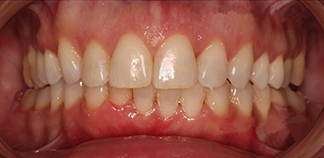

До лечения

Жалобы на скученность зубов.

Как лечили

Проведено ортодонтическое лечение на брекетах.

Лечащий врач

МАРЦИ Анастасия Викторовна